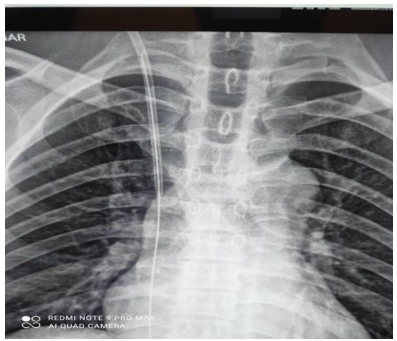

In the operating theatre, intravascular position of J-tip of guidewire was confirmed preoperatively with USG doppler and C-arm. Under General Anaesthesia, surgery was performed via inguinal approach. After pre-peritoneal fat layer was reached, extra-peritoneal dissection was continued. Position of J-tip of guidewire was determined with intraoperative USG (Figure 3). Vascular clamps were applied both proximal and distal to the J-tip. Phlebotomy was done in the right common iliac vein. Intact guidewire was retrieved without any complication apart from non-fatal arrhythmia

Figure 3: Intraoperative USG with J-Tip of guidewire in vessel lumen.